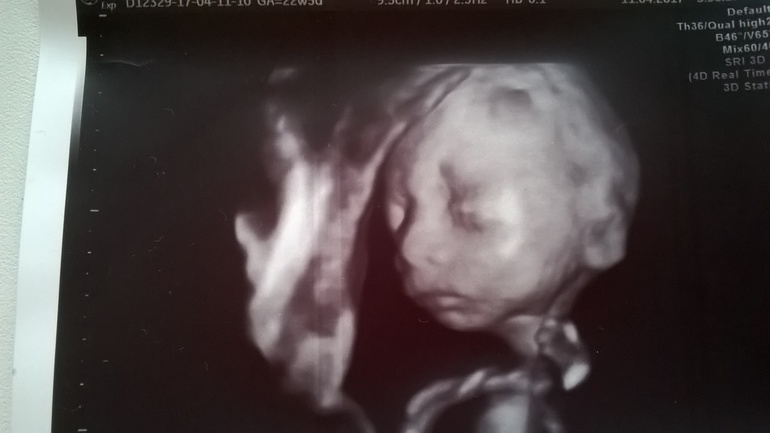

Второй кабинет и узи. Первый раз встретила очень хорошего узиста и бесплатно, дай бог здоровья этой женщине. Крутила и вертела она нас с лялькой. Все показатель в норме, вес у плода 547 Гр. Внутренние органы в норме, косточки, ручки, ножки, позвоночник, головка тоже все хорошо. Но ей надо было оценить нашу нижнюю челюсть. Лялька прятался и не довал это сделать. В итоге ей это получилось сделать, кучу фоток сделала она для комиссии, ну и мне одна досталась. Так сказать на память. Мы пришли с ней к мнению что да челюсть маленькая, но не критично и похожа на нашего старшего сына. Еще она мерила язык плода периметр 47 мм, а норма по книжкам для нашего срока гестации 52 мм, поставила она под вопросом гипоплозию языка и отправила на комиссию.

Теперь к вам вопрос девочки, выкладываю фото 3 д узи лицо нашего карапуза, не ужели все так плохо? Ну и для сравнения старший сын! Всем спасибо кто откликнется!![]()